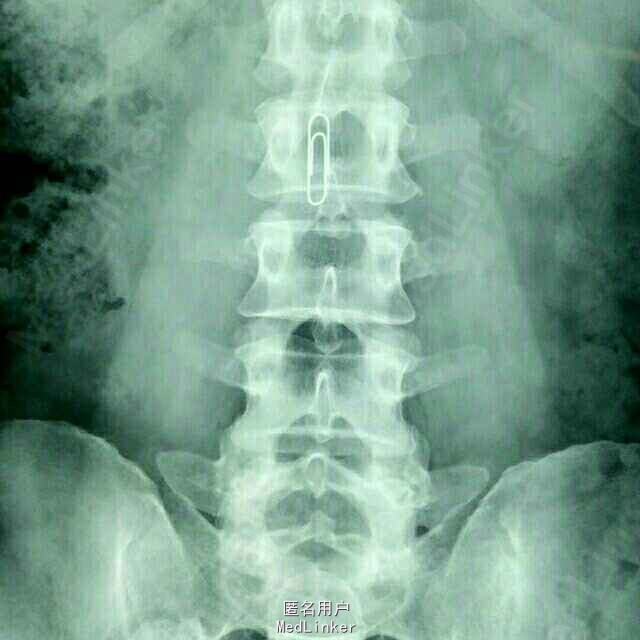

患者四肢肌力及肌张力可,病理反射未引出;鞍区及左侧大腿疼痛,无感觉减退。 腰椎MRI:腰2椎管内占位病变

患者四肢肌力及肌张力可,病理反射未引出;鞍区及左侧大腿疼痛,无感觉减退。 腰椎MRI:腰2椎管内占位

腰2神经鞘瘤 患者在全麻下行腰2椎管内占位病变切除术,术中见病变位于腰2神经马尾,呈囊实性,分界清,包裹神经纤维